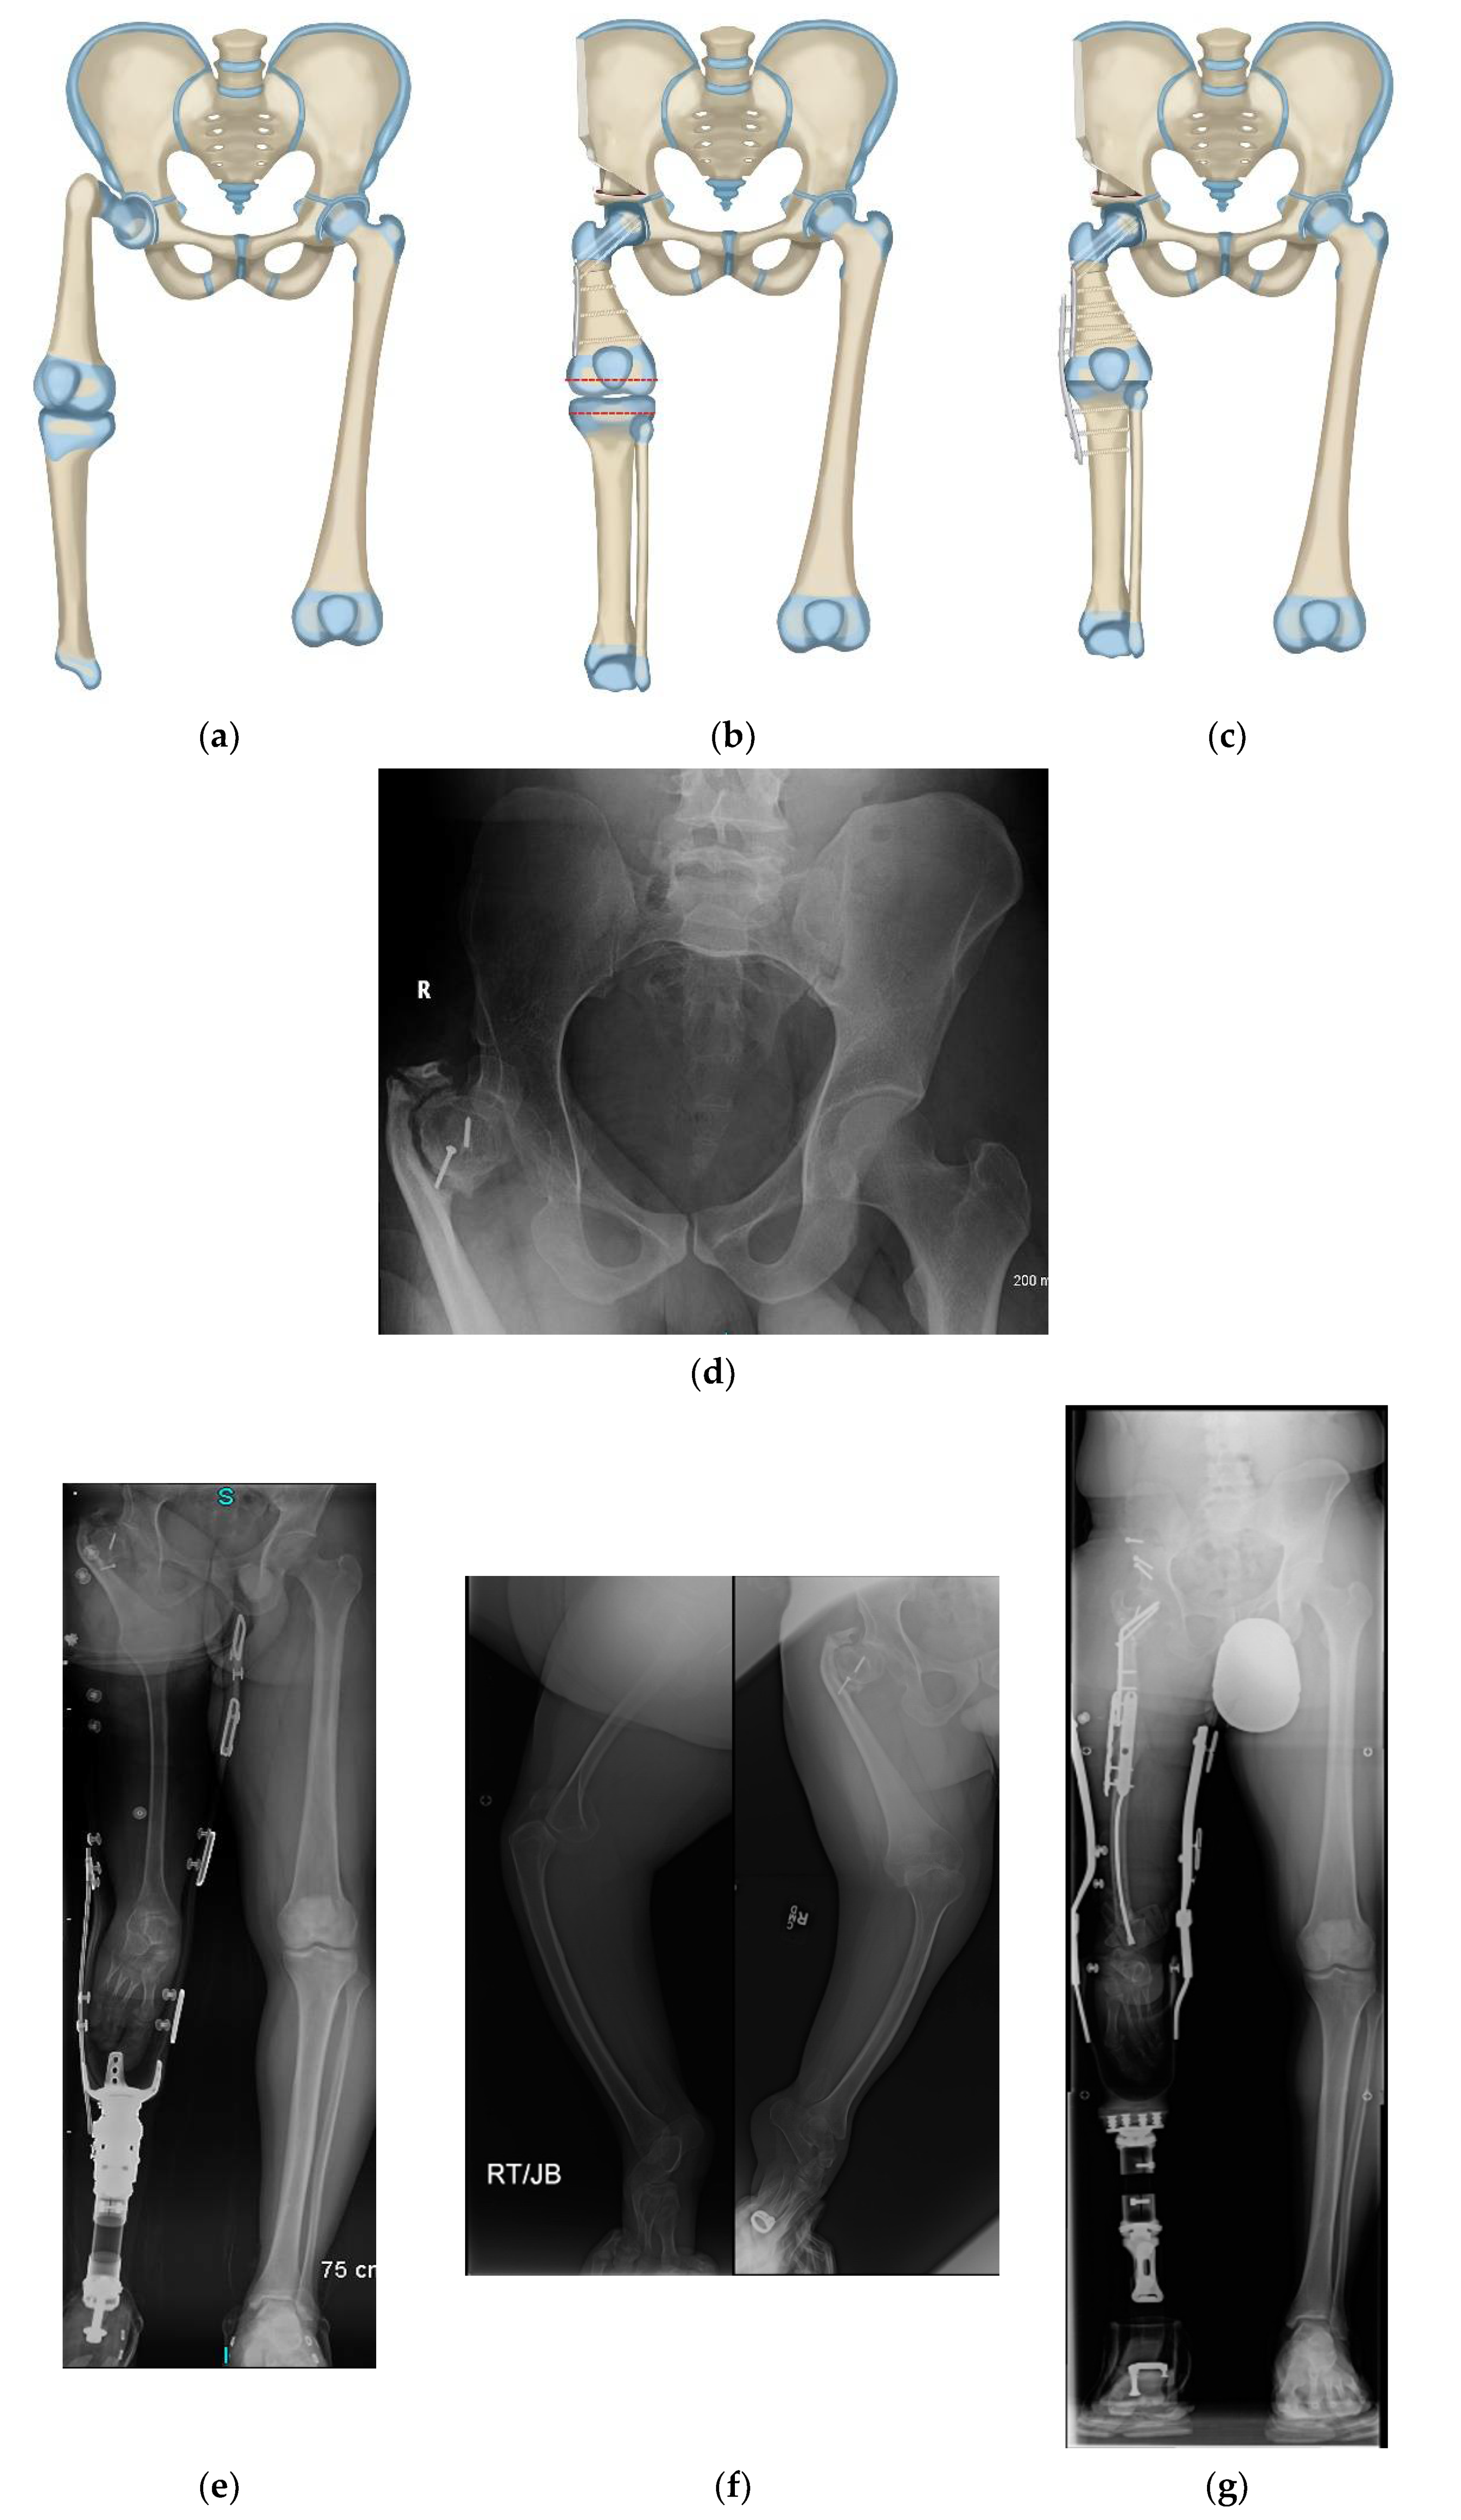

Figure 6.

(a) Illustration of CFD type 1a3 or 1b. (b) Illustration showing the first step which is SUPERhip procedure with resection of knee joint. (c) Illustration showing the second step which is PaleySUPERhip–Van Nes rotationplasty at level of the knee fusion. (d) AP pelvis on 36-year-old man with CFD type 1b with prior failed hip surgery. (e) Standing radiograph in same man showing ankle at level of opposite knee joint. (f) Long lateral and AP radiographs showing the knee joint in the same patient was unstable, deformed and subluxated. (g) Standing radiograph one year after PaleySUPERhip–Van Nes procedure including SUPERhip, knee fusion and supramalleolar osteotomy, wearing rotationplasty prosthetic. Ankle is at level of opposite knee. This procedure greatly improved his quality and of life, gait and function.